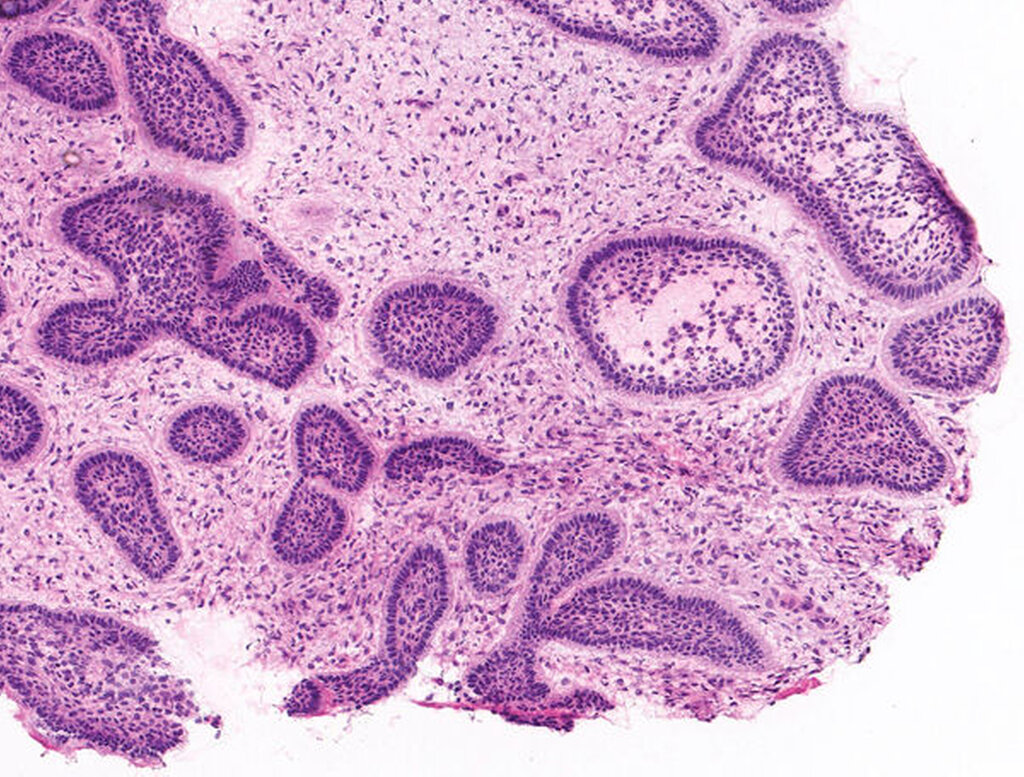

In der histopathologischen Schnellschnittuntersuchung zeigte sich in dem circa 3 cm x 2,5 cm messenden, größtenteils festen Resektat deutlich zellreiches, spindelzellig imponierendes mesenchymales Gewebe. Innerhalb dieses Präparats stellten sich einzelne dentogene Zielgruppen mit abgrenzender Palisadenstellung dar. Die weiterführende Untersuchung des gesamten Präparats im Rahmen der definitiven histologischen Befundung ergab zudem einen Hamartom-ähnlichen odontogenen Tumor, was schlussendlich zur Diagnose eines ameloblastischen Fibrodentinoms führte (Abbildungen 9 bis 11).